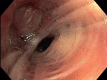

Figure 2

a) CT scan and b, c) 18F-FDG PET.